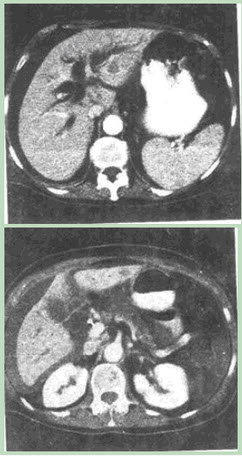

患者男性,49岁,反复腹痛,进行性黄疸月余,CT图像如下,最有可能的诊断是()。

C、胰头癌

C